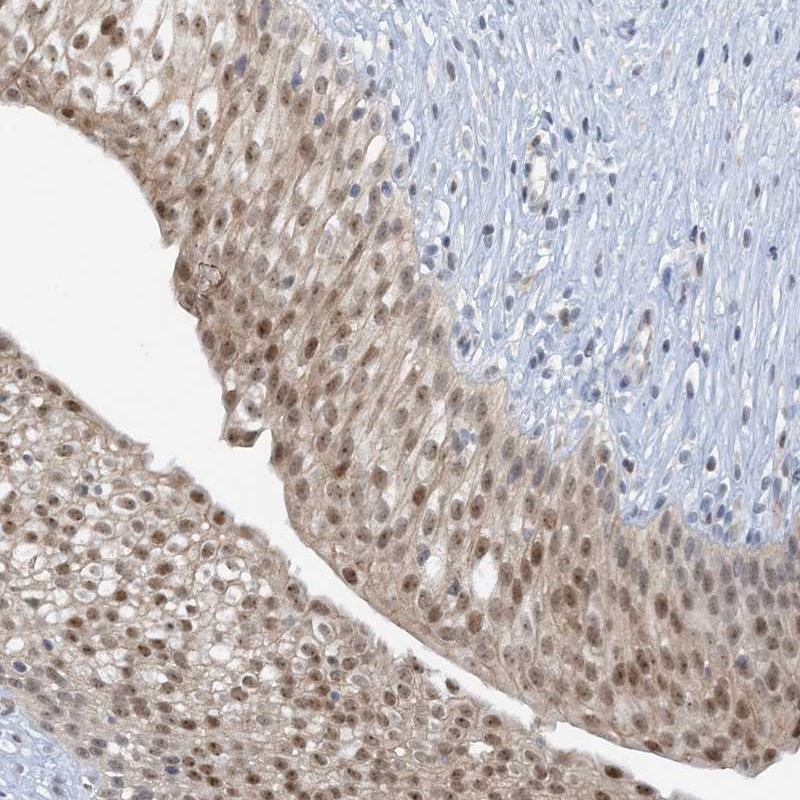

Immunohistochemical staining of human urinary bladder shows moderate nuclear positivity in urothelial cells.